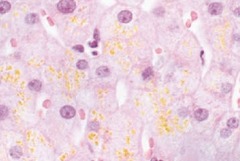

lipofuscin- pigment associated with aging

Front

what is the yellow-brown

Back